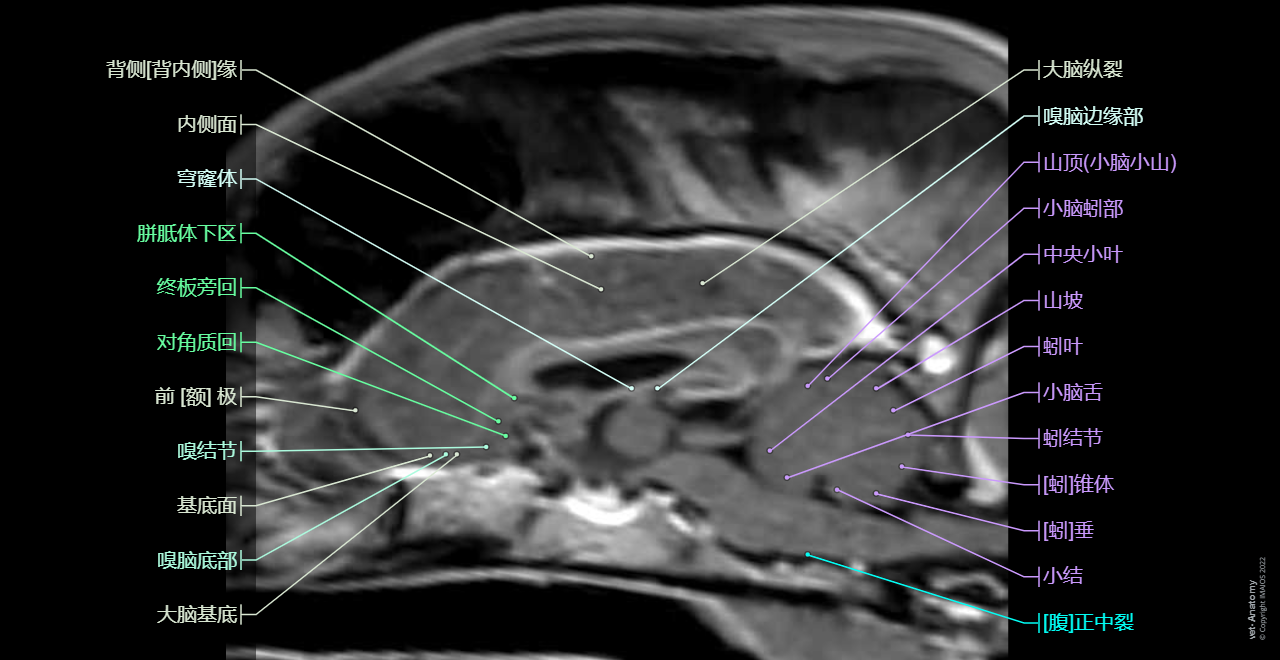

这vet-Anatomy单元主要包括狗头部MRI切片,展示超过400张图片。我们以1.5T MRI扫描一只健康的2岁拉布拉多犬,扫描图片按不同平面和加权分类:

- 22张采用了自旋回波的横向图像,有5种加权供以选择(FLAIR、T1、含钆造影剂的T1加权扫描、T2、T2加权)

- 3个图片系列(横向、矢状和背向),以多平面重组含钆造影剂的3D T1加权成像

一共有350个附注解的解剖结构,分布在以下各个部分:

- 区域

- 脑叶

- 脑

- 大体解剖

- 嗅脑

- 新皮质

- 白质

- 纹状体

- 间脑

- 中脑

- 小脑

- 脑桥

- 延髓

- 脊髓

- 颅神经

- 脑室

- 蛛网膜下池

- 腦脊膜

- 动脉

- 脑静脉

- 硬脑膜静脉窦

- 颅骨

这狗的脑部MRI解剖图是由来自荷兰乌特勒支的Dr. Susanne AEB Boroffka (dipl.ECVDI, PhD)所提供。Dr. Antoine Micheau和Dr. Denis Hoa(蒙彼利埃放射科医生)负责整理图片及解剖注解。感谢Pascal Fontaine先生的建议及对书目的贡献。

这里的解剖术语采用了国际兽医解剖学名词(2012第五版)上的拉丁语,由Imaios的Dr. Antoine Micheau翻译成英语和法语。